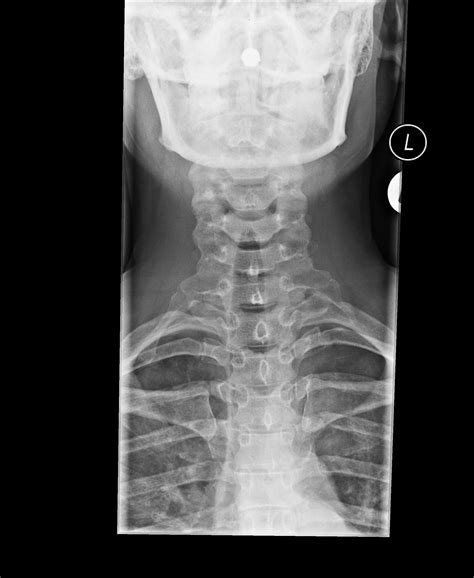

Что показывает рентген добавочного шейного ребра?